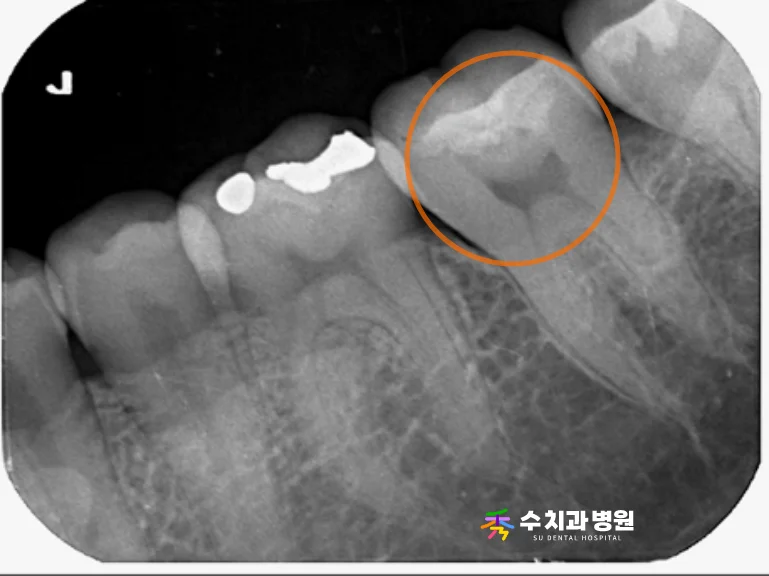

치료를 마무리하고 약 7개월이 지난 후,

정기검진을 위해 내원하셨을 때

방사선 촬영을 통해 상태를 점검했습니다.

[📸 치료 7개월 후 엑스레이사진] (촬영일: 2025년 6월)

검사 결과 신경치료를 진행한 뿌리 주변으로

염증 소견 없이 아주 안정적으로

잘 유지되고 있는 것을 확인했습니다.